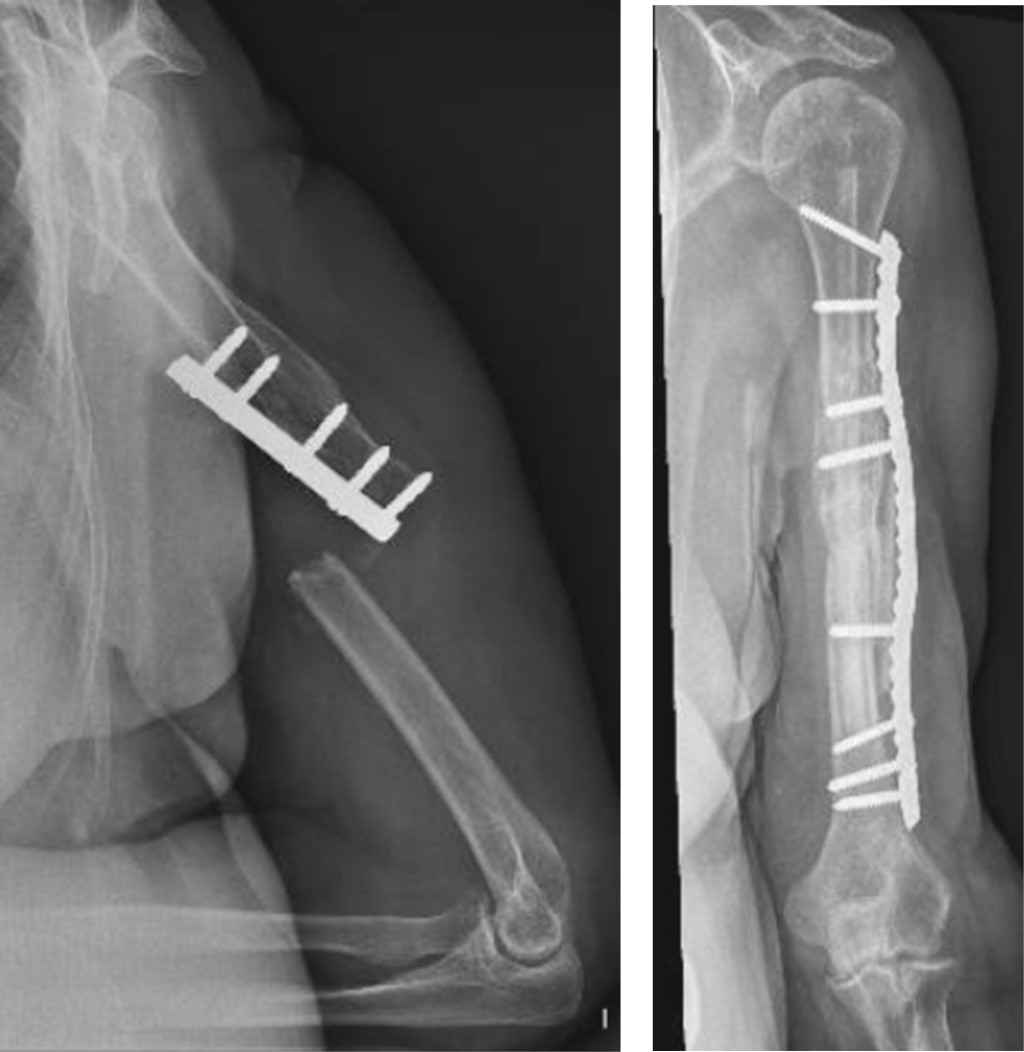

El miembro superior derecho estaba comprometido en nueve pacientes y el izquierdo en 13; el miembro dominante fue el afectado en 10 casos. El tercio proximal de la diáfisis humeral estaba involucrado en ocho pacientes, el tercio medio en otros ocho, el tercio distal en cuatro y dos pacientes presentaban no-consolidaciones segmentarias de la diáfisis humeral (Figura 1). El tiempo desde el trauma inicial hasta el tratamiento definitivo de la no-consolidación promedió 18 meses (rango: 6 a 51). El tratamiento inicial había sido conservador con yeso o brace termoplástico en cuatro pacientes y en 18 el tratamiento inicial fue quirúrgico; 12 pacientes habían tenido una cirugía previa, tres habían tenido dos cirugías previas, dos habían tenido tres cirugías con anterioridad y un paciente había tenido cuatro cirugías previas (Tabla 1). Al momento de realizar la última cirugía, ocho pacientes presentaban un dispositivo endomedular (seis clavos rígidos y dos clavos elásticos), nueve tenían una placa y en un paciente el implante había sido removido. En 16 de estos 17 casos los implantes fueron removidos en la cirugía definitiva; en un caso, que había sido tratado con clavo endomedular, en el cual la fractura evolucionó hacia la no-consolidación, la estabilización definitiva se realizó con una placa puente LCP larga de 3.5 mm, sin remover el clavo endomedular. Al momento de la cirugía definitiva, tres pacientes presentaban infección activa y tres presentaban antecedente de infección previa. Las reconstrucciones en los tres casos con infección activa fueron realizadas en dos etapas, siguiendo la técnica de la membrana inducida por cemento, descrita por Pelissier y colaboradores para reconstrucción de defectos óseos infectados (Figura 2).13

La estabilización definitiva se realizó utilizando clavos placa bloqueados de 4.5 mm en 12 no-consolidaciones (siete localizadas en el tercio proximal de la diáfisis, dos segmentarias y tres del tercio medio de la diáfisis humeral); placas de compresión bloqueadas (LCP) de 4.5 mm en cinco no-consolidaciones (cinco diafisarias y una del tercio proximal de la diáfisis); en el paciente en el que el clavo endomedular no fue removido, se utilizó una placa LCP de 3.5 mm y se utilizaron dos placas en las cuatro no-consolidaciones del tercio distal de la diáfisis humeral. El largo de las placas promedió 21.38 centímetros (rango: 10.88 a 26.2). El número de orificios de las placas promedió 12.56 (rango: 10 a 16) (Tabla 3); en todos los casos en que se utilizó clavos placa bloqueados o placas LCP, se colocaron de manera híbrida, combinando tornillos de compresión a ambos lados de la no-consolidación primero (para comprimir el foco de no-consolidación), seguidos de tornillos bloqueados a continuación. En los tres pacientes que presentaban infección activa se realizó la reconstrucción en dos etapas, utilizando espaciadores de cemento impregnados con antibiótico (gentamicina y dos gramos de vancomicina) en la primera etapa; el espaciador con antibióticos fue colocado paralelo a la no-consolidación en dos casos e intramedular en el tercer caso. El tiempo entre la colocación del espaciador y el segundo tiempo quirúrgico, en el que se realizó la reconstrucción definitiva, fue de tres meses en los tres casos.

En pacientes con no-consolidación diafisaria de húmero, el uso de fijación interna con placas combinado con injerto autólogo ha evidenciado elevados porcentajes de consolidación y pocas complicaciones.6 Resultados disimiles han sido publicados en no-consolidaciones de húmero tratadas mediante cambio de clavos endomedulares fallidos;19,20,21 mientras que la revisión con placas en no-consolidaciones diafisarias humeral tratadas inicialmente con clavos endomedulares ha demostrado resultados mejores y más predecibles.22,23 Diversas técnicas han sido descritas para mejorar la fijación interna en hueso osteoporótico, incluyendo placas bloqueadas, combinación de implantes, aumento con cemento, la asociación de tablas de aloinjerto o el cambiar tornillos corticales flojos de 4.5 mm por tornillos de esponjosa de 6.5 mm; todas estas técnicas son útiles y cada una tiene ventajas y desventajas.10 En nuestra serie, clavos placa bloqueados de 4.5 mm se utilizaron en no-consolidaciones que afectaban el tercio proximal de la diáfisis (ocho casos), en no-consolidaciones segmentarias (dos casos) y en no-consolidaciones medio-diafisarias en las que se consideró necesario usar implantes con buen anclaje en la cabeza humeral (dos casos). El uso de clavos placa bloqueados es técnicamente demandante, pero tiene la ventaja de permitir mayor agarre y estabilidad proximal, aspecto de gran relevancia en hueso osteoporótico.7 En los 22 casos se utilizaron placas largas, puenteando el área afectada por implantes previos; el uso de placas largas permitió incrementar la resistencia al arranque de los implantes, incrementar su largo de trabajo y flexibilidad.22

Las no-consolidaciones infectadas están frecuentemente asociadas a pérdida ósea, cirugías previas con implantes flojos o rotos, fístulas activas, pobre vascularización de los extremos óseos, pobre calidad ósea y rigidez de las articulaciones vecinas.36 La técnica de la membrana inducida por cemento, descrita por Masquelet y que consiste en la reconstrucción en etapas, siendo la primera la colocación de un espaciador de polimetilmetacrilato (PMMA) a nivel de la no-consolidación, tiene ventajas mecánicas porque permite rellenar los espacios muertos previniendo la invasión del área afectada por tejido fibroso poco vascularizado, ayuda a mantener la anatomía normal (alineación y largo del hueso) y ayuda a mantener el trofismo de los extremos óseos, mientras prepara una seudomembrana rica en factores de crecimiento y osteoconductivos, que va a servir como lecho receptor bien vascularizado para la colocación del injerto óseo al momento de remover el PMMA.37,38 En los tres casos con infección activa de nuestra serie utilizamos esta técnica, colocando espaciadores de PMMA con gentamicina y dos gramos de vancomicina en la etapa inicial; el uso de antibióticos en el cemento permite administrar altas dosis de antibióticos locales con mínima distribución sistémica;39,40,41 en estos tres casos se erradicó la infección y se obtuvo la consolidación.